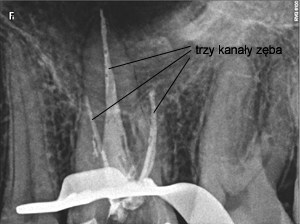

Pacjent lat 28 trafił do naszego gabinetu z powodu z powodu ćmiących dolegliwości bólowych zęba trzonowego górnego. Był on uprzednio leczony endodontycznie, lecz nie spowodowało to ustąpienia objawów. Po skierowaniu na leczenie endodontyczne przy użyciu mikroskopu zabiegowego uwidoczniono dodatkowy – czwarty i piąty kanał zęba. Po opracowaniu chemo – mechanicznym całego systemu korzeniowego i wypełnieniu kanałów termiczną gutaperką dolegliwości ustąpiły a ząb został odbudowany ze wzmocnieniem włóknem szklanym. Takie standardowe postępowanie lecznicze często obecnie wzbogacane o diagnostykę trójwymiarową 3D przy użyciu tomografii wolumetrycznej CBCT pozwala na jeszcze skuteczniejszą terapię endodontyczną i eliminację bólów często pierwotnie trudnych do zdiagnozowania i wyleczenia.